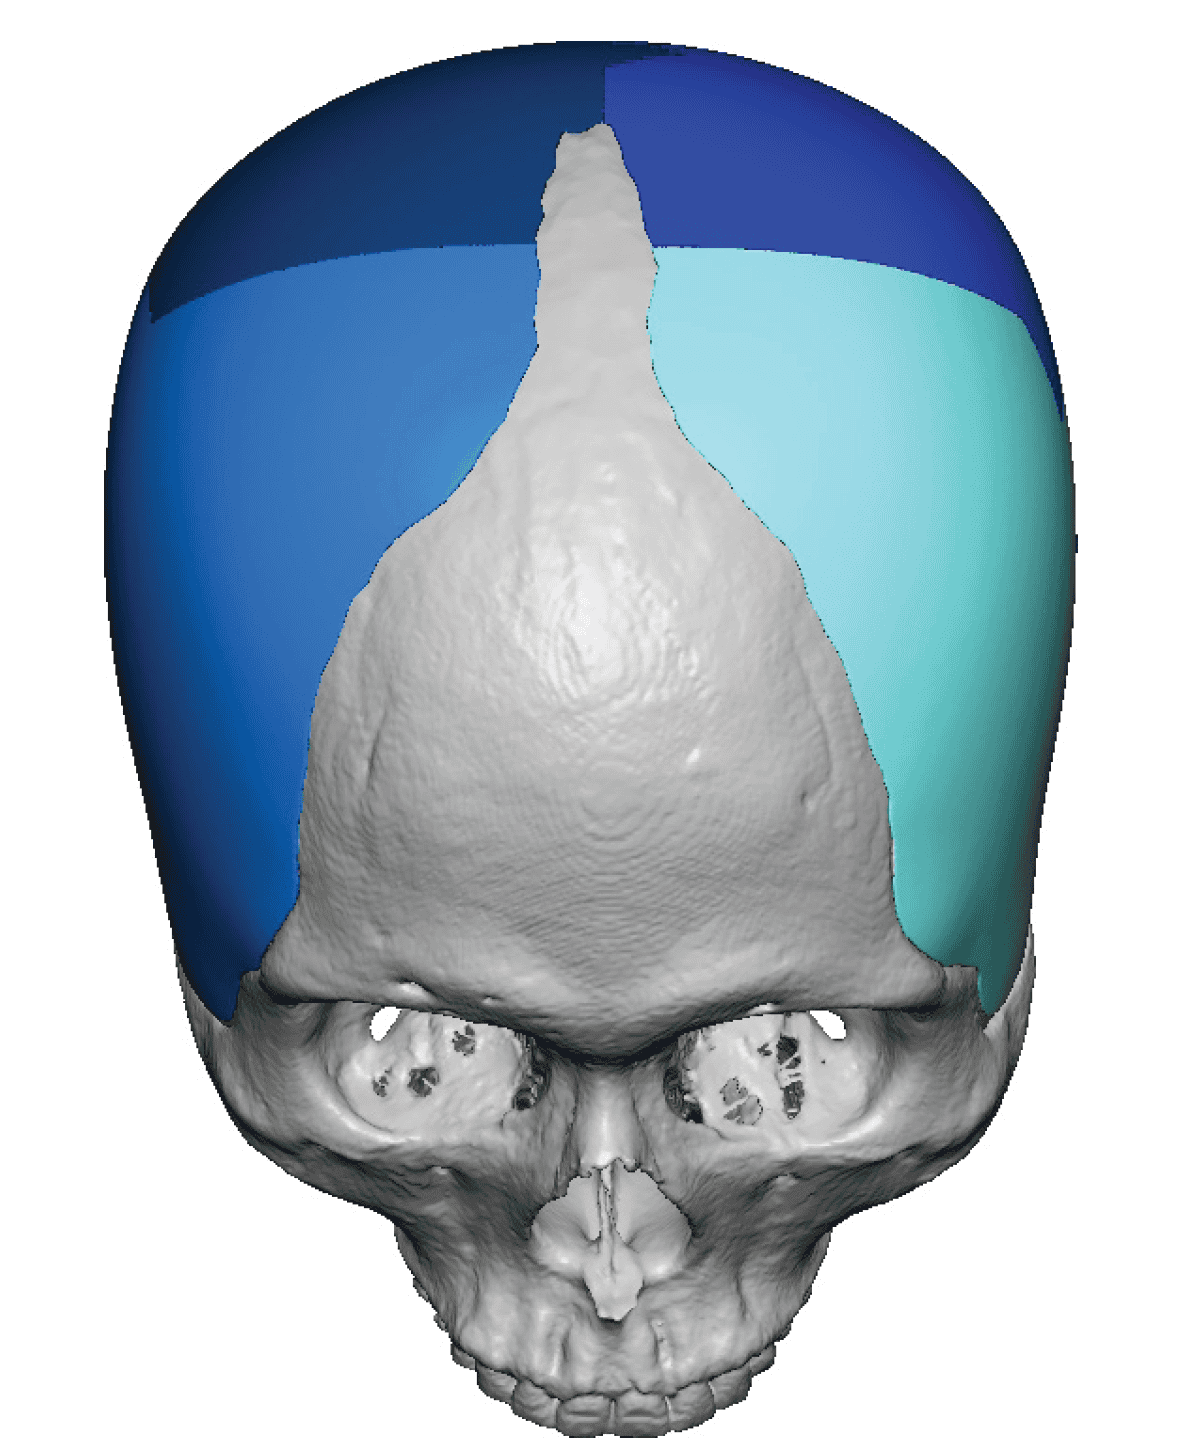

Desire for change of head shape from front view form an inverted V shape to a rounder and wider head shape.

Placement of custom extended forehead-temporal implants through incisions in the crease behind the ear. (he had a prior back of head skull implant which is green in the implant designs and which the head widening implants partially covered it)

Desire for change of head shape from front view form an inverted V shape to a rounder and wider head shape.

Placement of custom extended forehead-temporal implants through incisions in the crease behind the ear. (he had a prior back of head skull implant which is green in the implant designs and which the head widening implants partially covered it)